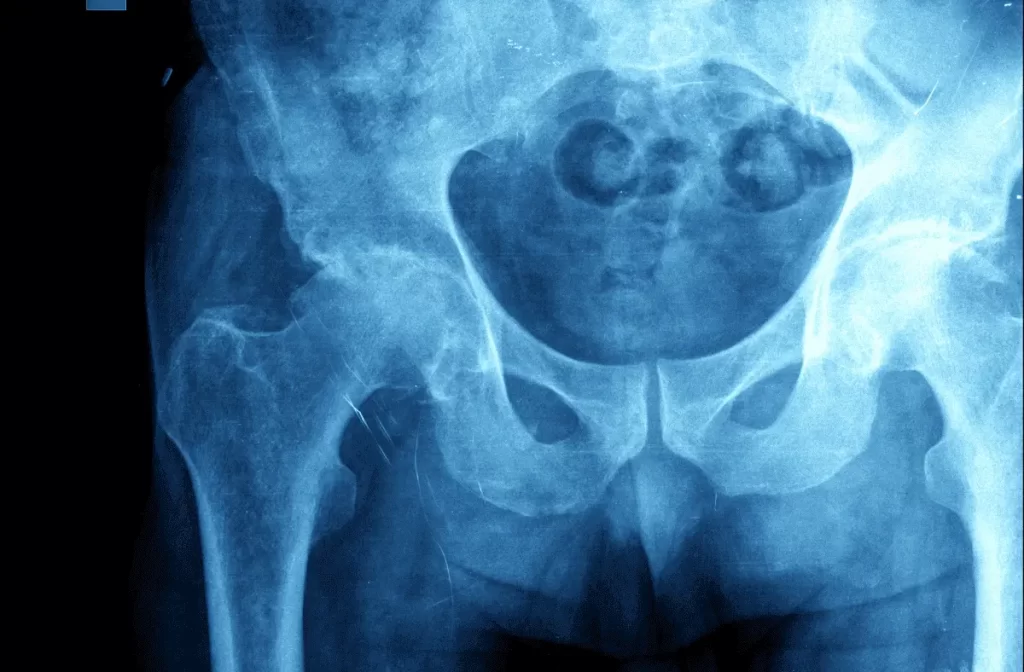

Broken Hip

While the injuries are often attributed to falls and trauma, some cases of broken bones can be traced back to osteoporosis.

In most cases, surgery will be the likely treatment option.

It will however depend on the fracture’s location in the femur.